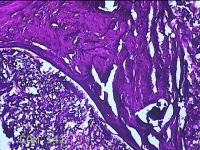

下颌部包块

性别

男

年龄

47岁

临床诊断

皮脂腺囊肿

一般病史

发现下颌部包块3年余,无疼痛及不适。

标本名称

大体所见

灰白暗红色带皮肤结节1.5x1.3x0.8cm一个,表面糜烂,切开结节呈实性,切面灰白粉红色,质软。

图3